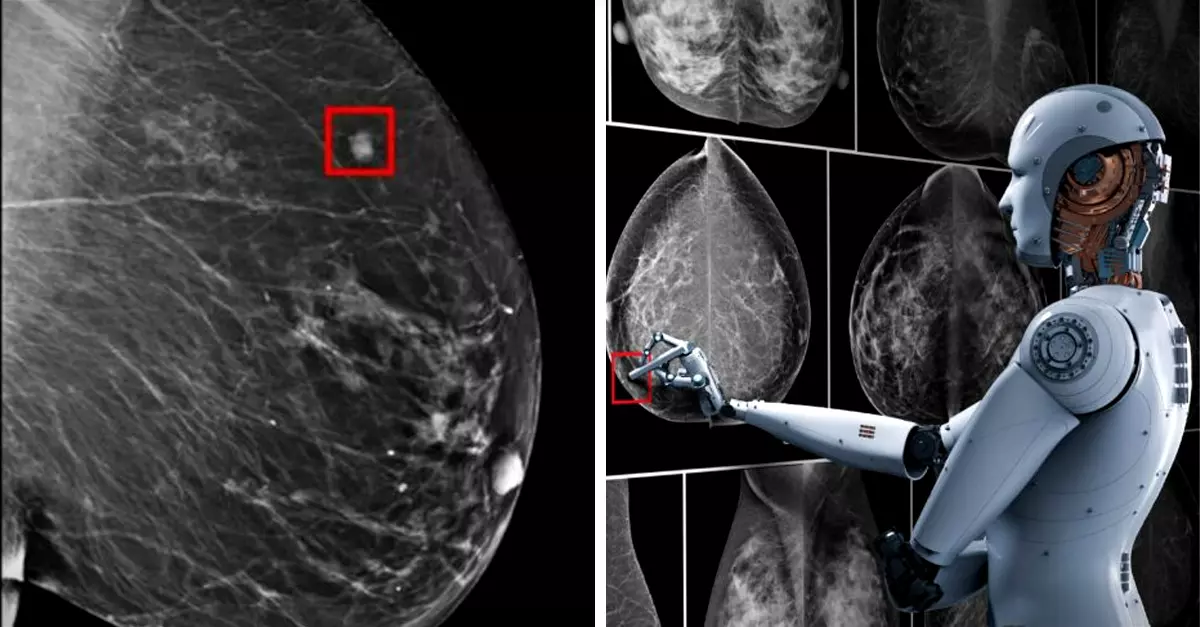

Sin embargo, podría haber un cambio y un gran avance en cuanto a la detección temprana, ya que unos investigadores de Massachusetts, Estados Unidos, descubrieron que con ayuda de un aparato con Inteligencia Artificial (IA) se podría predecir el cáncer de mama hasta cinco años de que empiece a manifestarse.

Esta deducción surgió tras una investigación realizada por científicos del Hospital General de Massachusetts y el Laboratorio de Ciencias e Inteligencia Artificial del Instituto de Tecnología de Massachusetts (MIT, por sus siglas en inglés), quienes, tras desarrollar un modelo de predicción basado en el aprendizaje profundo (deep learning), detectaron sutiles patrones que podrían lograr prever las posibilidades del desarrollo de cáncer.

Este método de IA, desarrollado por la profesora Regina Barzilay, logró reconocer sutiles patrones del tejido mamario. El avance podría prever las posibilidades de padecerlo hasta cinco años de manifestar síntomas. Además, en un futuro, permitirá la creación de tratamientos más personalizados y facilitará el seguimiento, adaptándose a las necesidades y riesgos específicos de cada paciente.